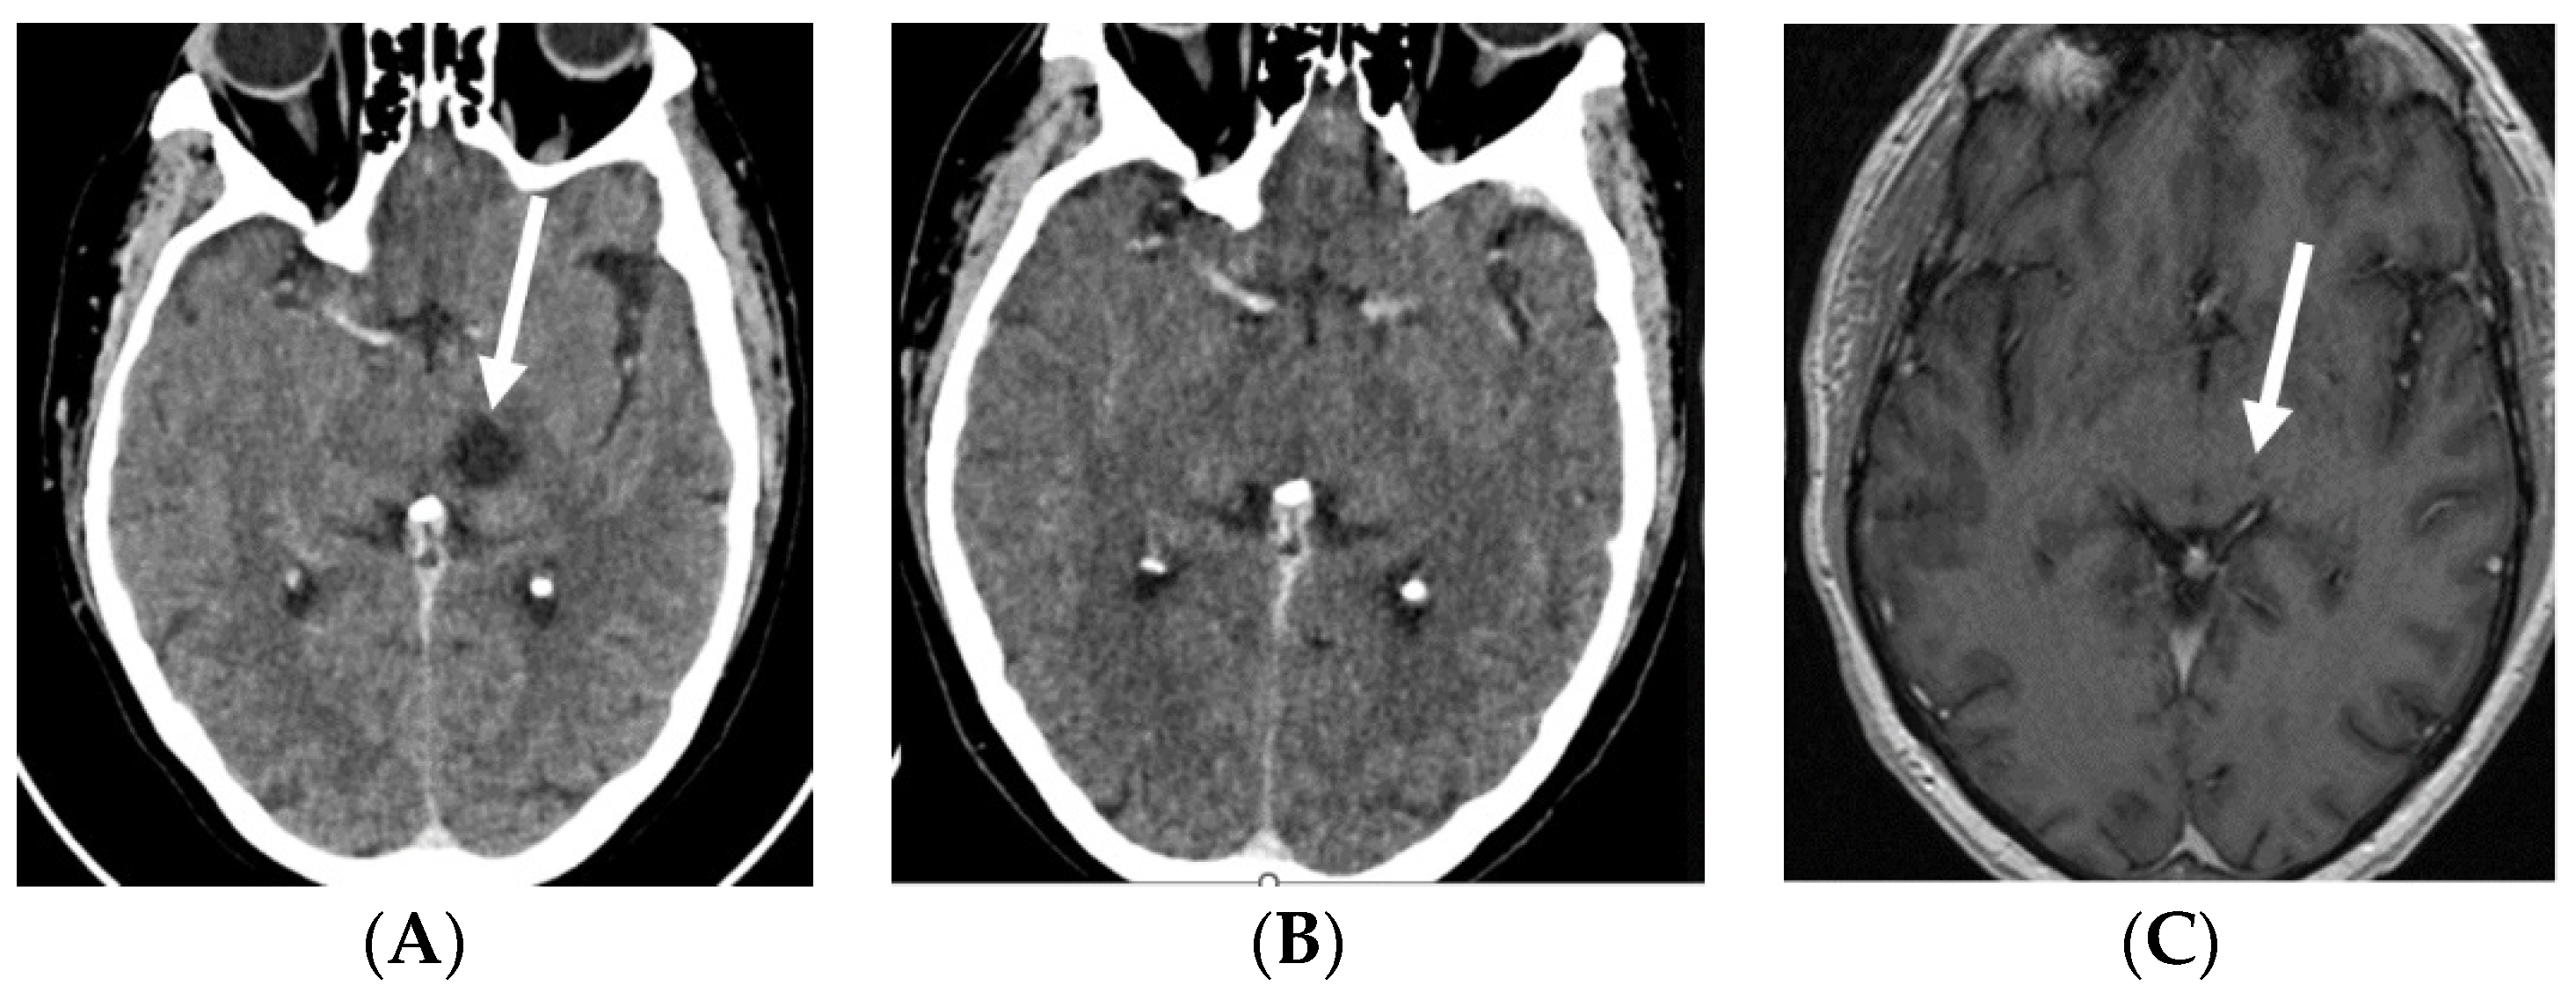

2.1. Case 1